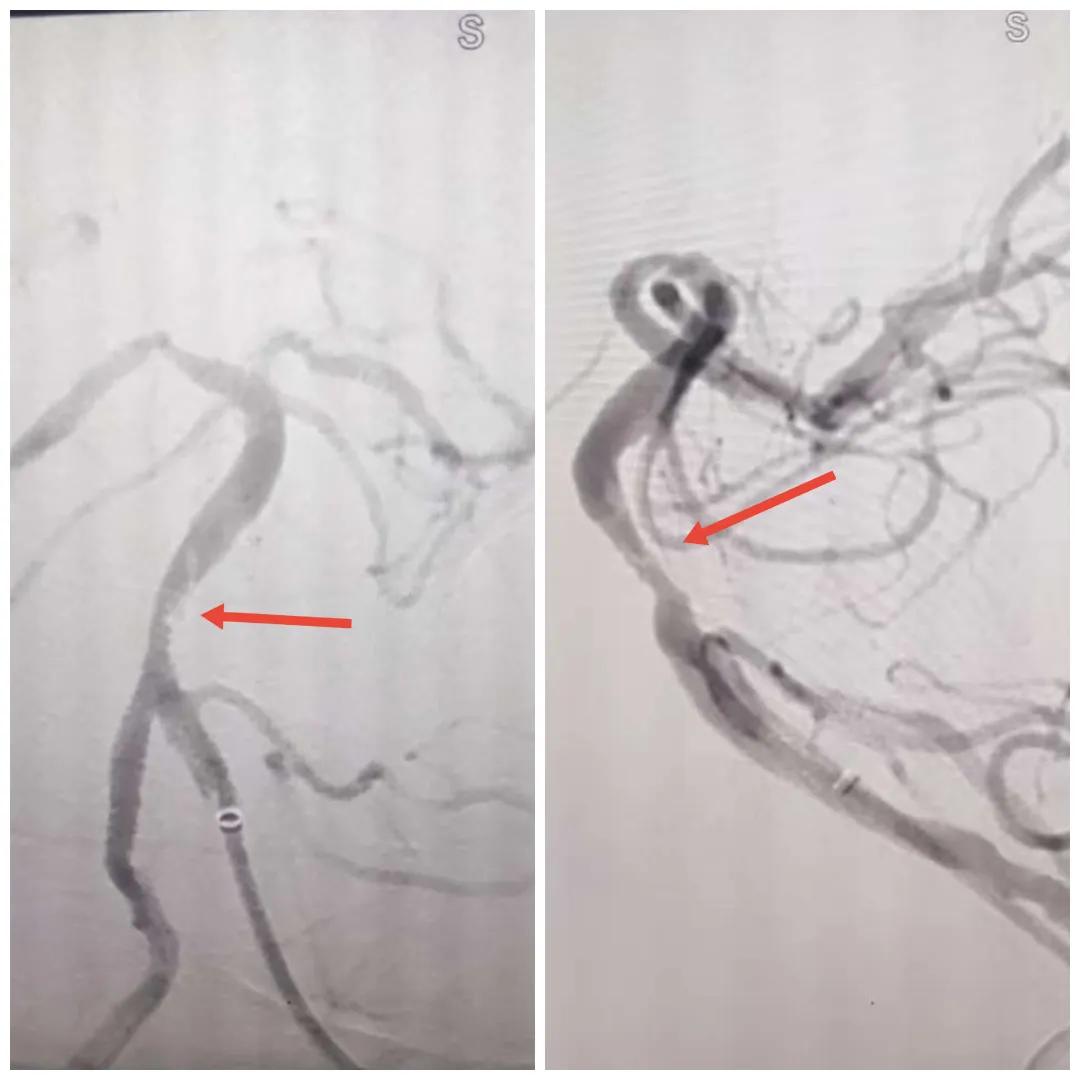

在經(jīng)造影后,主刀醫(yī)生腦一科副主任楊慶堂發(fā)現(xiàn)患者基底動(dòng)脈下段重度狹窄且狹窄段以遠(yuǎn)有大負(fù)荷血栓,其狹窄處考慮為動(dòng)脈夾層,手術(shù)難度及風(fēng)險(xiǎn)較大。楊慶堂副主任在彭壯副主任醫(yī)師的協(xié)助下運(yùn)用spaceman(太空人)技術(shù),中間導(dǎo)管抵近血栓抽吸配合支架拉栓,成功開(kāi)通血管。再次造影可見(jiàn)基底動(dòng)脈管腔明顯增寬,遠(yuǎn)端血管顯影良好,且等待20分鐘后造影仍顯示血流通暢。楊慶堂副主任考慮到本次手術(shù)時(shí)間不宜過(guò)長(zhǎng),現(xiàn)患者基底動(dòng)脈及分支前向血流維持良好,給予其抗栓藥物應(yīng)用后結(jié)束手術(shù),并建議患者3個(gè)月后復(fù)查造影,明確其基底動(dòng)脈夾層情況。

取栓后血管管腔增寬,前向血流良好